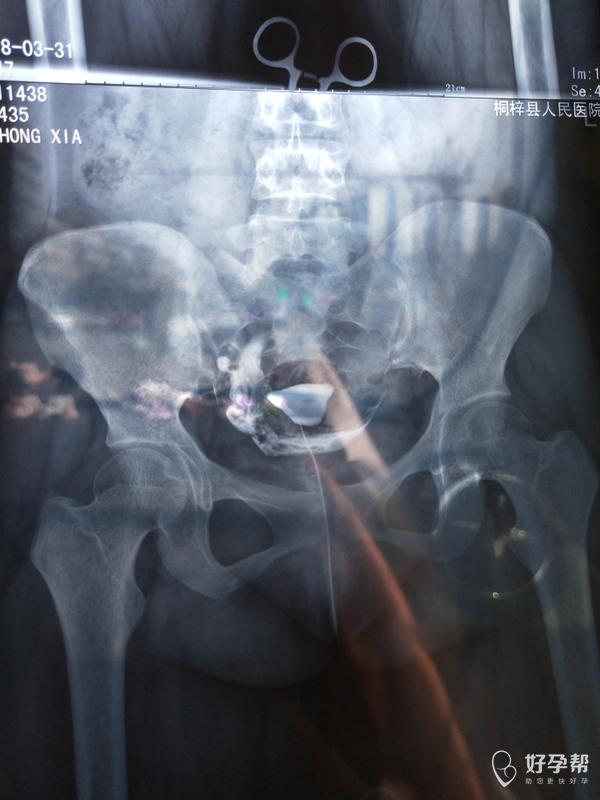

医生 看看我的输卵管造影

输卵管堵塞一是手术,二是试管婴儿。建议直接试管婴儿。